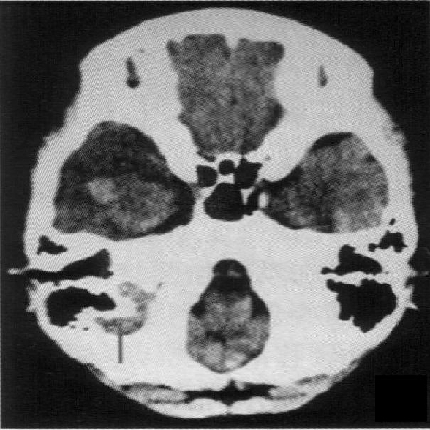

标题: PED1818:男,13岁。头痛5天,复视、呕吐3天。体检:神经生 [打印本页]

标题: PED1818:男,13岁。头痛5天,复视、呕吐3天。体检:神经生

右中颅窝见囊性占位影,其中央见块状高密度影,高密度块后后缘见条状钙化?前部与殘存颞叶皮质相连,临近骨质无异常,病灶囊变区呈长t1长t信号,实性区呈中等信号,增强(最后两副是增强t1像吧)有明显强化,实性块影上部尚见鸟嘴状影(比较像脑膜尾),考虑右中颅窝脑膜瘤可能性大,不排除室管膜瘤,畸胎瘤等

病理:囊性脑膜瘤